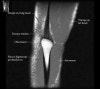

- Sagittal section

1) Biceps Brachii tendon and Brachiallis muscles

2) Radial head for radiographically occult fractures

3) Distal Triceps tendon